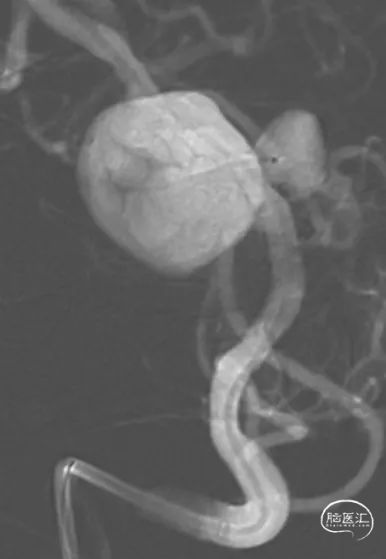

FRED支架释放后,支架CT提示支架贴壁良好

使用25×50、25×50 axium弹簧圈栓塞基底动脉瘤后,使用14×40、10×30、8×30、5×20、3×8 5枚弹簧圈栓塞椎动脉瘤及闭塞左椎动脉末端

经左椎动脉造影,弹簧圈最终完全闭塞左椎动脉V4段,附近的脊髓后动脉保留

经右椎动脉最终造影

术后3个月MRA复查提示:支架内血流通畅,动脉瘤体积进一步缩小。准备6-12月期间复查脑血管造影